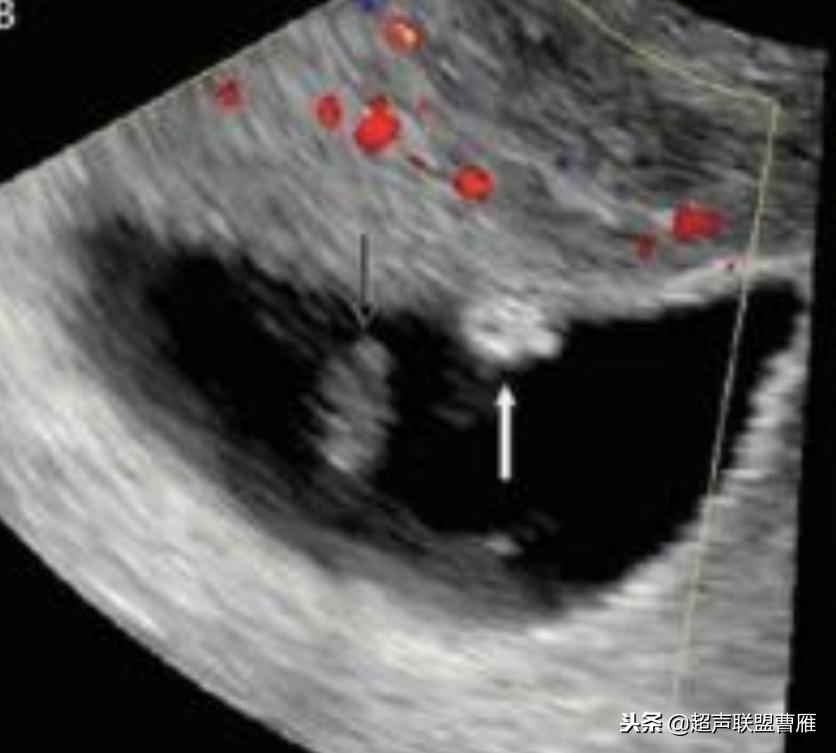

钙化卵黄囊6.6mm,一周后胚胎死亡

卵黄囊回声增强,预后不良

卵黄囊钙化